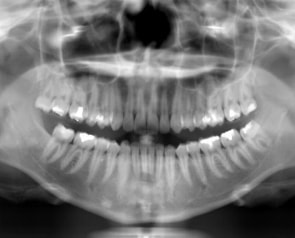

高精細なデジタルCTレントゲンを完備!

患者様に負担をかけず、状況を詳しく知ること!

デジタルCTパノラマレントゲンは今まで大学病院等に行かなければ撮影できなかったCT・パノラマ画像を院内にて撮影することができます。

デジタルX線センサーは超高感度で照射時間を短縮!

撮影範囲も設定可能で低線量にて高精細のレントゲン画像取得が可能となります。

子供さんにも優しいレントゲンです!

※フィルムを使用した撮影に比べ、人体に受ける放射線の量を、約1/4~1/10に抑える事が可能です。

また、従来行われていたレントゲン写真の現像などの手間もなくなり、画像も各ユニットモニターに表示され、ご一緒に見ることが可能!

それにより精細な状況説明や治療方針もお伝えできます。

デジタルCTレントゲン導入により環境にも優しく、スピーディーな対応が可能となりました。